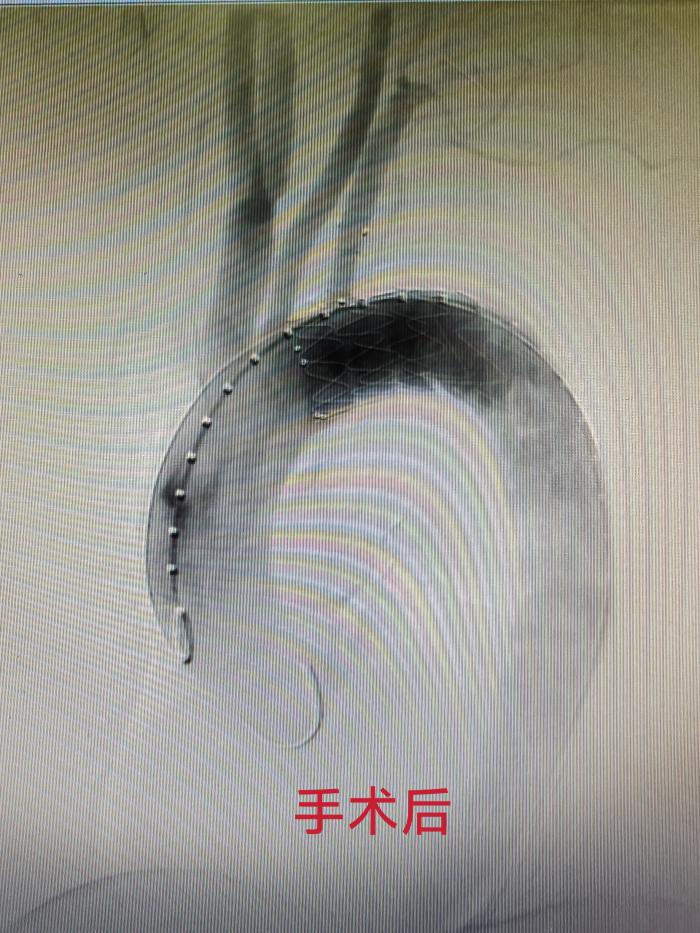

面对锚定困难、易内漏等多重手术难点,周定中主任带领介入血管外科团队开展周密术前评估,在与患者及家属充分沟通后,决定采用一种新型分支型支架。该支架具备独特的主动式“鸟嘴”调节功能,能完美适配患者复杂病情,此次应用为湘南地区首例。

手术由龙文兴主任医师主刀,实施胸主动脉腔内介入修复术。凭借精湛的操作技术,结合新型支架的优异性能,手术顺利攻克各项难题。术后造影显示,血管破口被完全封堵,假腔无血流通过,支架贴壁牢固、无移位及内漏,重要分支血管供血通畅,手术取得圆满成功。

该微创手术无需开胸,仅通过大腿根部微小穿刺创口,即可将支架精准送至病变部位修复血管,具有创伤小、出血少、恢复快等优势。术后患者无并发症,恢复情况良好,仅住院一周于4月7日顺利康复出院。